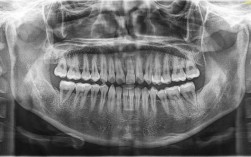

(二)曲面断层片

- 牙根:全牙列牙根形态正常,无弯曲、吸收,11、21牙根尖周无低密度影;

- 牙槽骨:牙槽骨嵴高度正常,11、21、12、22牙槽骨水平吸收至根中1/3(与牙根倾斜相关),余牙槽骨吸收至根尖1/3;

- 发育状况:第三磨牙牙胚存在(18、28、38、48),位置正常,未萌出。